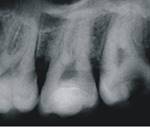

En 2011 concurre paciente de sexo masculino, de 22 años, por caries profunda en pieza 38. Radiográficamente se destaca la cercanía de la cavidad cariosa con respecto a la amplia cámara pulpar (Fig. 3a). Se diagnostica CPPA, luego de eliminar la dentina necrótica reblandecida superficial con cucharita de dentina y verificar su vitalidad con test de fresado. En la evaluación dentinaria se constata dentina de color marrón, blanda y húmeda. Se planifica Técnica de eliminación de caries en etapas. La Fig.3b muestra eliminación total de caries de paredes laterales con control colorimétrico sin tocar la pared pulpar.